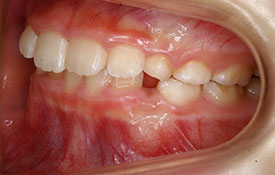

インビザラインの治療例:CASE-2

| プロフィール | 15歳 男性 |

| 所見 | アメリカから転院されて来られた方です。 インビザラインで上下顎の矯正治療を開始し下顎はアメリカで終了しており、上顎のみ治療の後期を担当しました。 アイライナーの装着は、1日平均22時間ほどでした。 |